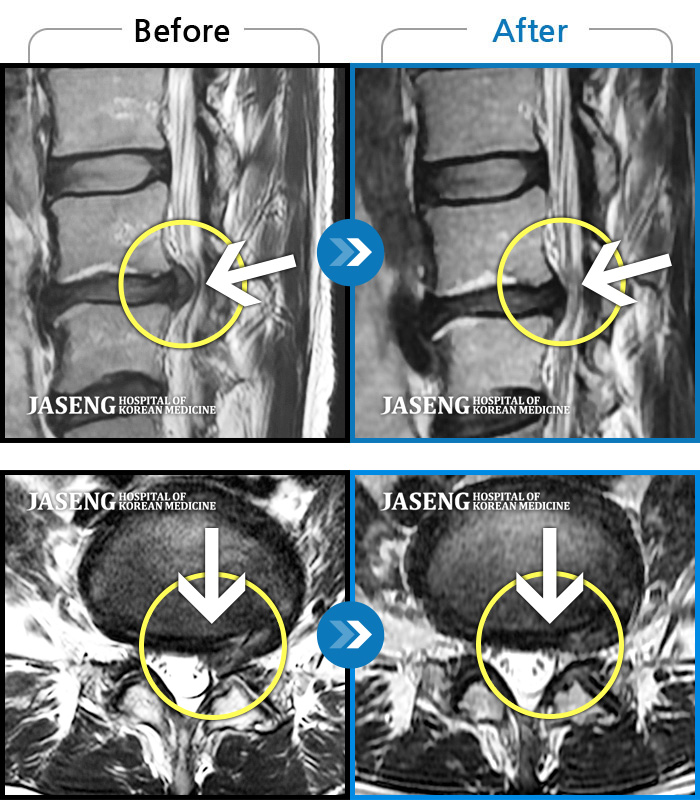

ȯںп Ǹ ǿ ԿǾ, ο ġ ۿ Ƿ ġḦ Ͻñ ٶϴ.